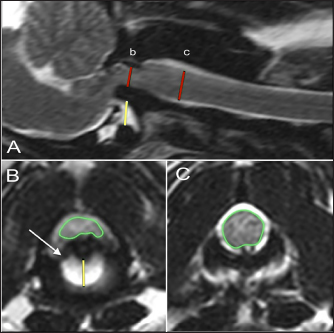

MRI characteristics were evaluated categorically and numerically. To evaluate spinal cord compression, a cross-sectional percentage of the spinal cord was calculated by outlining the spinal cord diameter at the level of the dens compared to its size at the level of the mid-body of C2 on the imaging software program (Figs. 1B and C and 2B and C). The degree of AA joint subluxation was identified as the size of the AA joint cavity, using a sagittal measurement of the distance from the ventral border of the dens or the most rostral portion of C2 to the caudal articular fovea of the atlas (Figs. 1A and 2A), and a transverse measurement from the ventral border of the dens or rostral C2 to the dorsal margin of the atlas (Figs. 1B and 2B). The integrity of apical, alar, and transverse ligaments was assessed as present (Fig. 2B), absent, or inconclusive based on the previous protocol established by Middleton et al. (2012).

Fig. 1. T2-weighted sagittal (A) and transverse (B, C) images of a 3-year-old spayed female Maltese with acute tetraplegia (TE, 120 ms; TR, 3800 ms; slice thickness, 2.5 mm). On the sagittal image (A), the dorsoventral diameter of the spinal cord at the level of the dens (b) and mid-body of C2 (c) has been measured (red lines), as has the distance from the ventral border of the dens to the caudal articular fovea of the atlas (yellow line). On the transverse images, the cross-sectional area of the spinal cord at the level of the dens (B) and mid-body of C2 (C) has been outlined, as has the subluxation distance from the dens to the atlas (yellow line in B). This dog had dorsally and cranially displaced dens present, as well as an overlapping C1. The transverse ligament was present (white arrow in B).